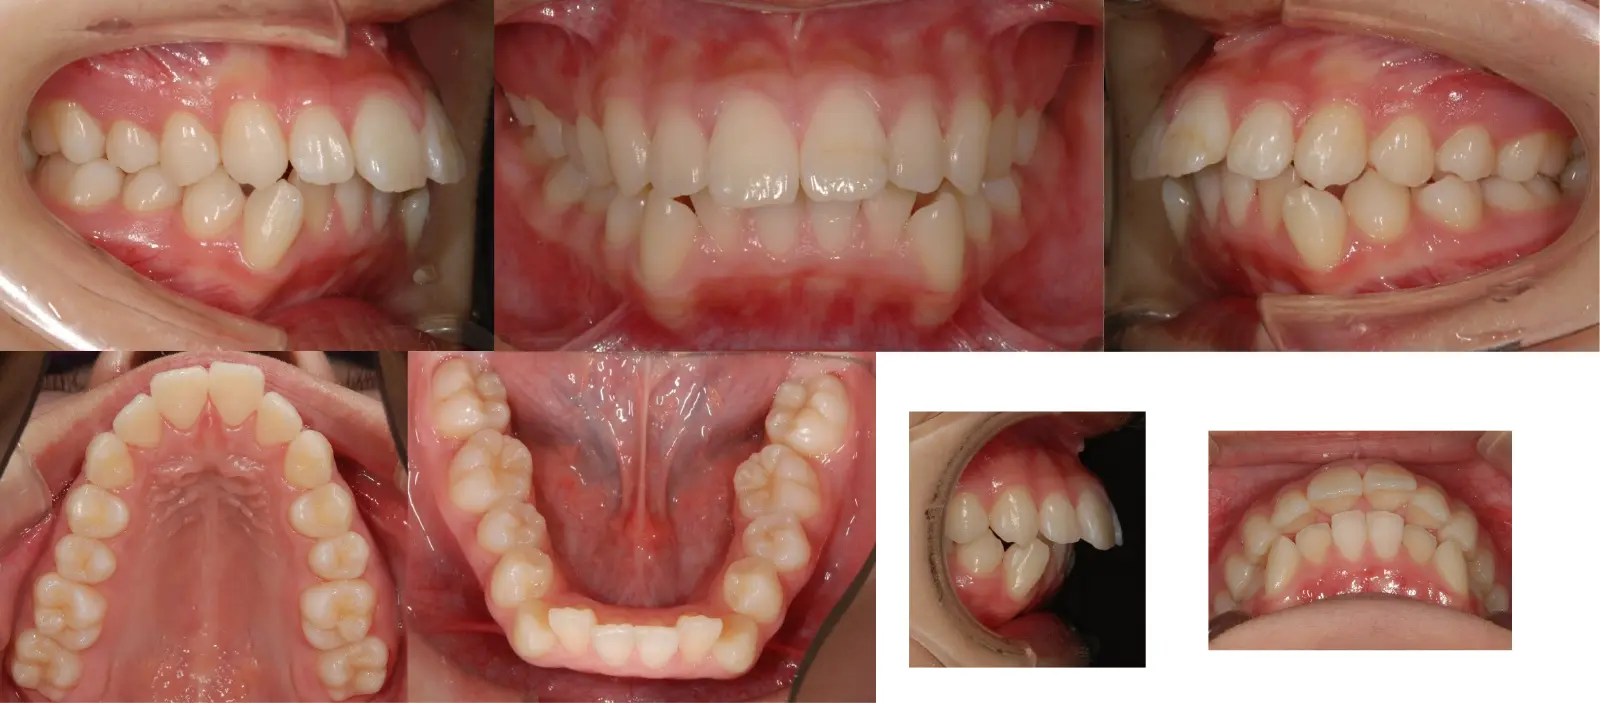

アングルⅡ級 叢生を伴う上顎前突症

- 主訴

前歯がかみ合わない、突出している

- 年齢

10代

- 治療期間

1年4ヶ月

- 治療回数

14回

- 治療に用いた主な装置

カスタムメイド型マルチブラケットタイプのデジタル矯正装置(インシグニア)

TAD(ミニスクリュー)を上顎臼歯部に植立

- 治療費

600,000円(税別)、調整料5,000円(税別)

※伊那分院にて治療

- 抜歯部位

上下顎第一小臼歯 計4本